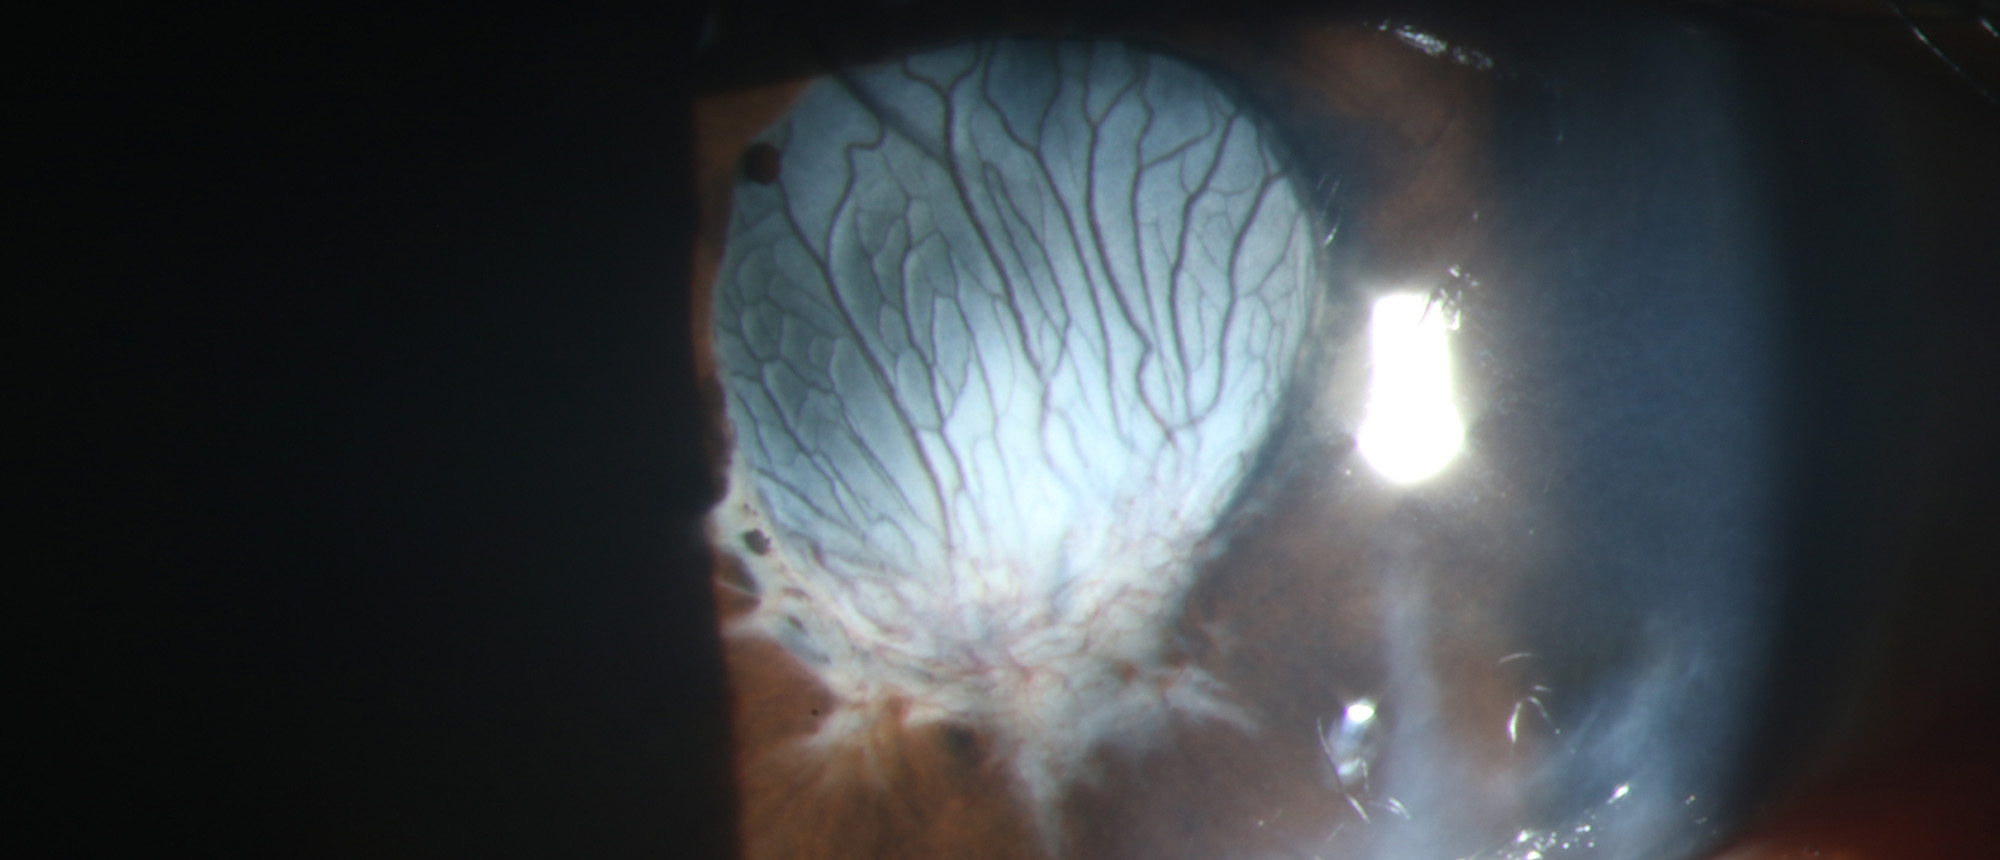

A patient with atypical presentation of toxoplasma chorioretinitis. Ultra wide field color fundus photograph showing a peripheral retinal whitening with patchy areas of active inflammation underlying a grade 2 vitreous haze in the left eye at presentation. The patient was initially suspected of acu…